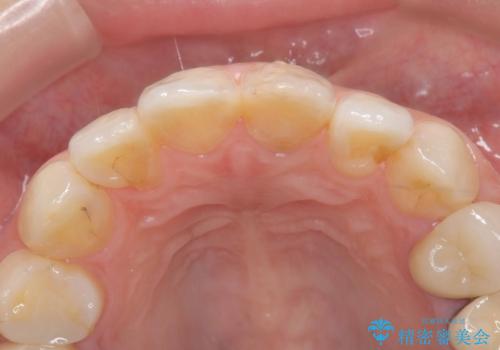

前歯にプラスチックの材料が入っており、形と色が悪くなっていました。

失活歯だったため全体的に歯の色が暗くなっていました。

右上1もCRが入っており治療を勧めましたが、希望されず左上1のみ行いました。